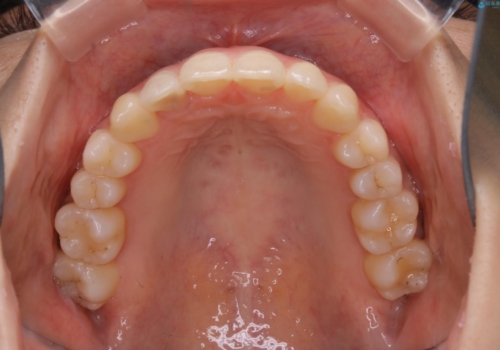

非抜歯でも劇的変化 インビザライン矯正治療

歯のガタつきを治すため矯正治療を希望。審査の結果、非抜歯での矯正が可能であるという見通しが立ったためインビザラインによる非抜歯矯正治療を行った。

歯を並べるスペースを作るために、歯の遠心移動と歯列の拡大、歯自体を少しだけ小さく削る(IPR)という方法を複合的に組み合わせて配列を行いました。遠心移動用のゴムかけにはマイクロインプラントという小さいネジを用いて骨に直接固定源を求めました。